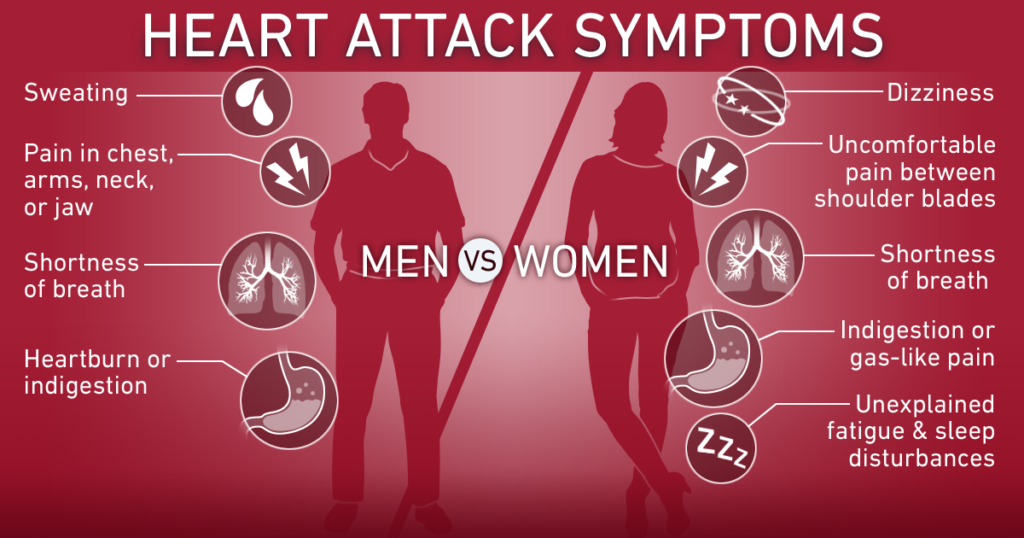

হার্ট অ্যাটাকের লক্ষণ বা উপসর্গসমূহ

নিঃশ্বাস বন্ধ হয়ে আসা অথবা শ্বাসকষ্ট হতে পারে।

বমি বমি ভাব অথবা বমি হতে পারে।

বুকে মারাত্মক তীব্র ব্যথা হতে পারে।

বুকে চাপ অনুভুত হওয়া, যন্ত্রণা হওয়া কিংবা ভারী ভারী লাগা।

বিষম খাওয়া।

শরীরে প্রচুর পরিমানে ঘাম হতে পারে।

খাবার হজমে সমস্যা হবে এবং পেটের উপরের অংশে জ্বালাপোড়া করতে পারে।

চোখে ঝাপসা দেখা, অন্ধকার দেখা ইত্যাদি সমস্যা হতে পারে।

হার্ট অ্যাটাকে আক্রান্ত হলে রোগী অজ্ঞান হয়ে যেতে পারে।